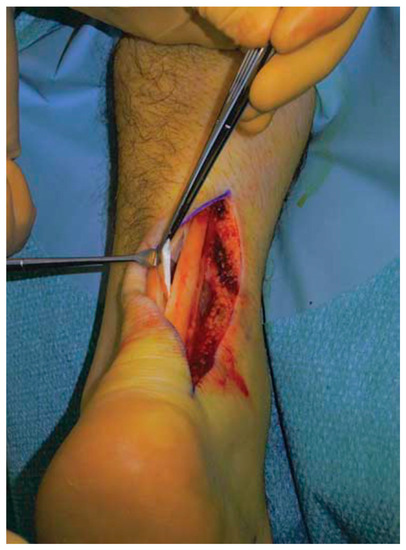

Figure 8.

Flexor hallucis longus tendon graft was harvested through a 2.5 to 3 cm longitudinal medial incision along the distal portion of the Achilles tendon.